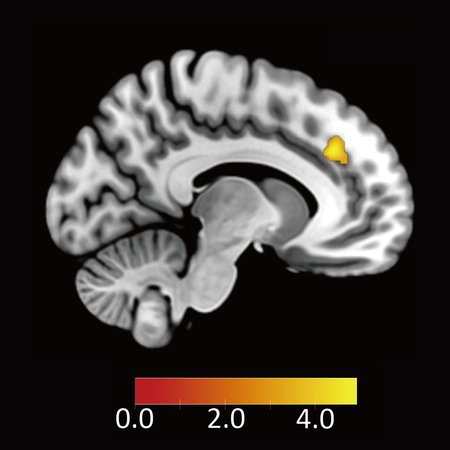

次に、不公平な条件が提示されたときに、この背側前帯状皮質が抑制的に働くと考えられる脳領域、すなわち負の結合度を示す領域を探索したところ、腹外側前頭前野が見つかりました(図3B参照)。さらに、背側前帯状皮質と腹外側前頭前野の結合度から、各参加者が不公平な提案を受け入れる割合(拒否率、図3C参照)と、反応時間(図3D参照)の両方を予測できることが分かりました。一方で、報酬に関わる脳活動からは、このような予測はできませんでした。

図3(A)不公平な提案を受け入れる参加者ほど不公平に対して反応する脳領域(背側前帯状皮質)

(B)Aの脳領域と負の結合度を示す領域(腹外側前頭前野)

(C)背側前帯状皮質と腹外側前頭前野の結合度と不公平な提案の拒否率及び(D)反応時間。結合度が行動選択と反応時間を予測することがわかる。結合度がマイナスの大きな値を取るほど受け入れる率が高く、反応時間も短くなる。